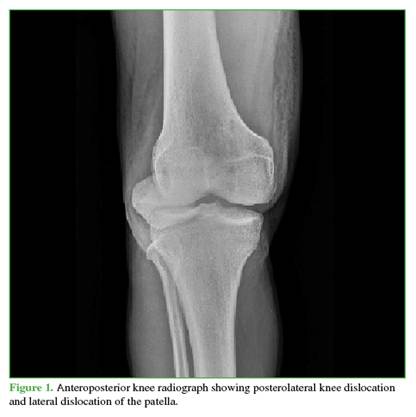

A 27-year-old male farmer residing in a rural area, with no relevant medical history, suffered a traffic accident after falling into a ravine while riding a motorcycle, resulting in trauma to his right shoulder and knee. He initially sought care at a rural hospital, where marked edema, ecchymosis, and a positive dimple sign were identified in the right knee. He also had limited range of motion in both the shoulder and the knee. As X-rays were not available, he was referred to a hospital with orthopedic services. There, initial radiographs were obtained (Figures 1 and 2), documenting a diaphyseal humeral fracture that was immobilized with a sugartong splint. In addition, a posterolateral knee dislocation and a lateral patellar dislocation were diagnosed. Two orthopedic surgeons attempted three reductions under sedation (no anesthesia was available), successfully reducing the patella but not the knee. It was decided that the patient required transfer to a trauma center for urgent open reduction and to rule out an associated vascular injury. The knee was immobilized with a bivalved hip-to-foot splint and he was referred.